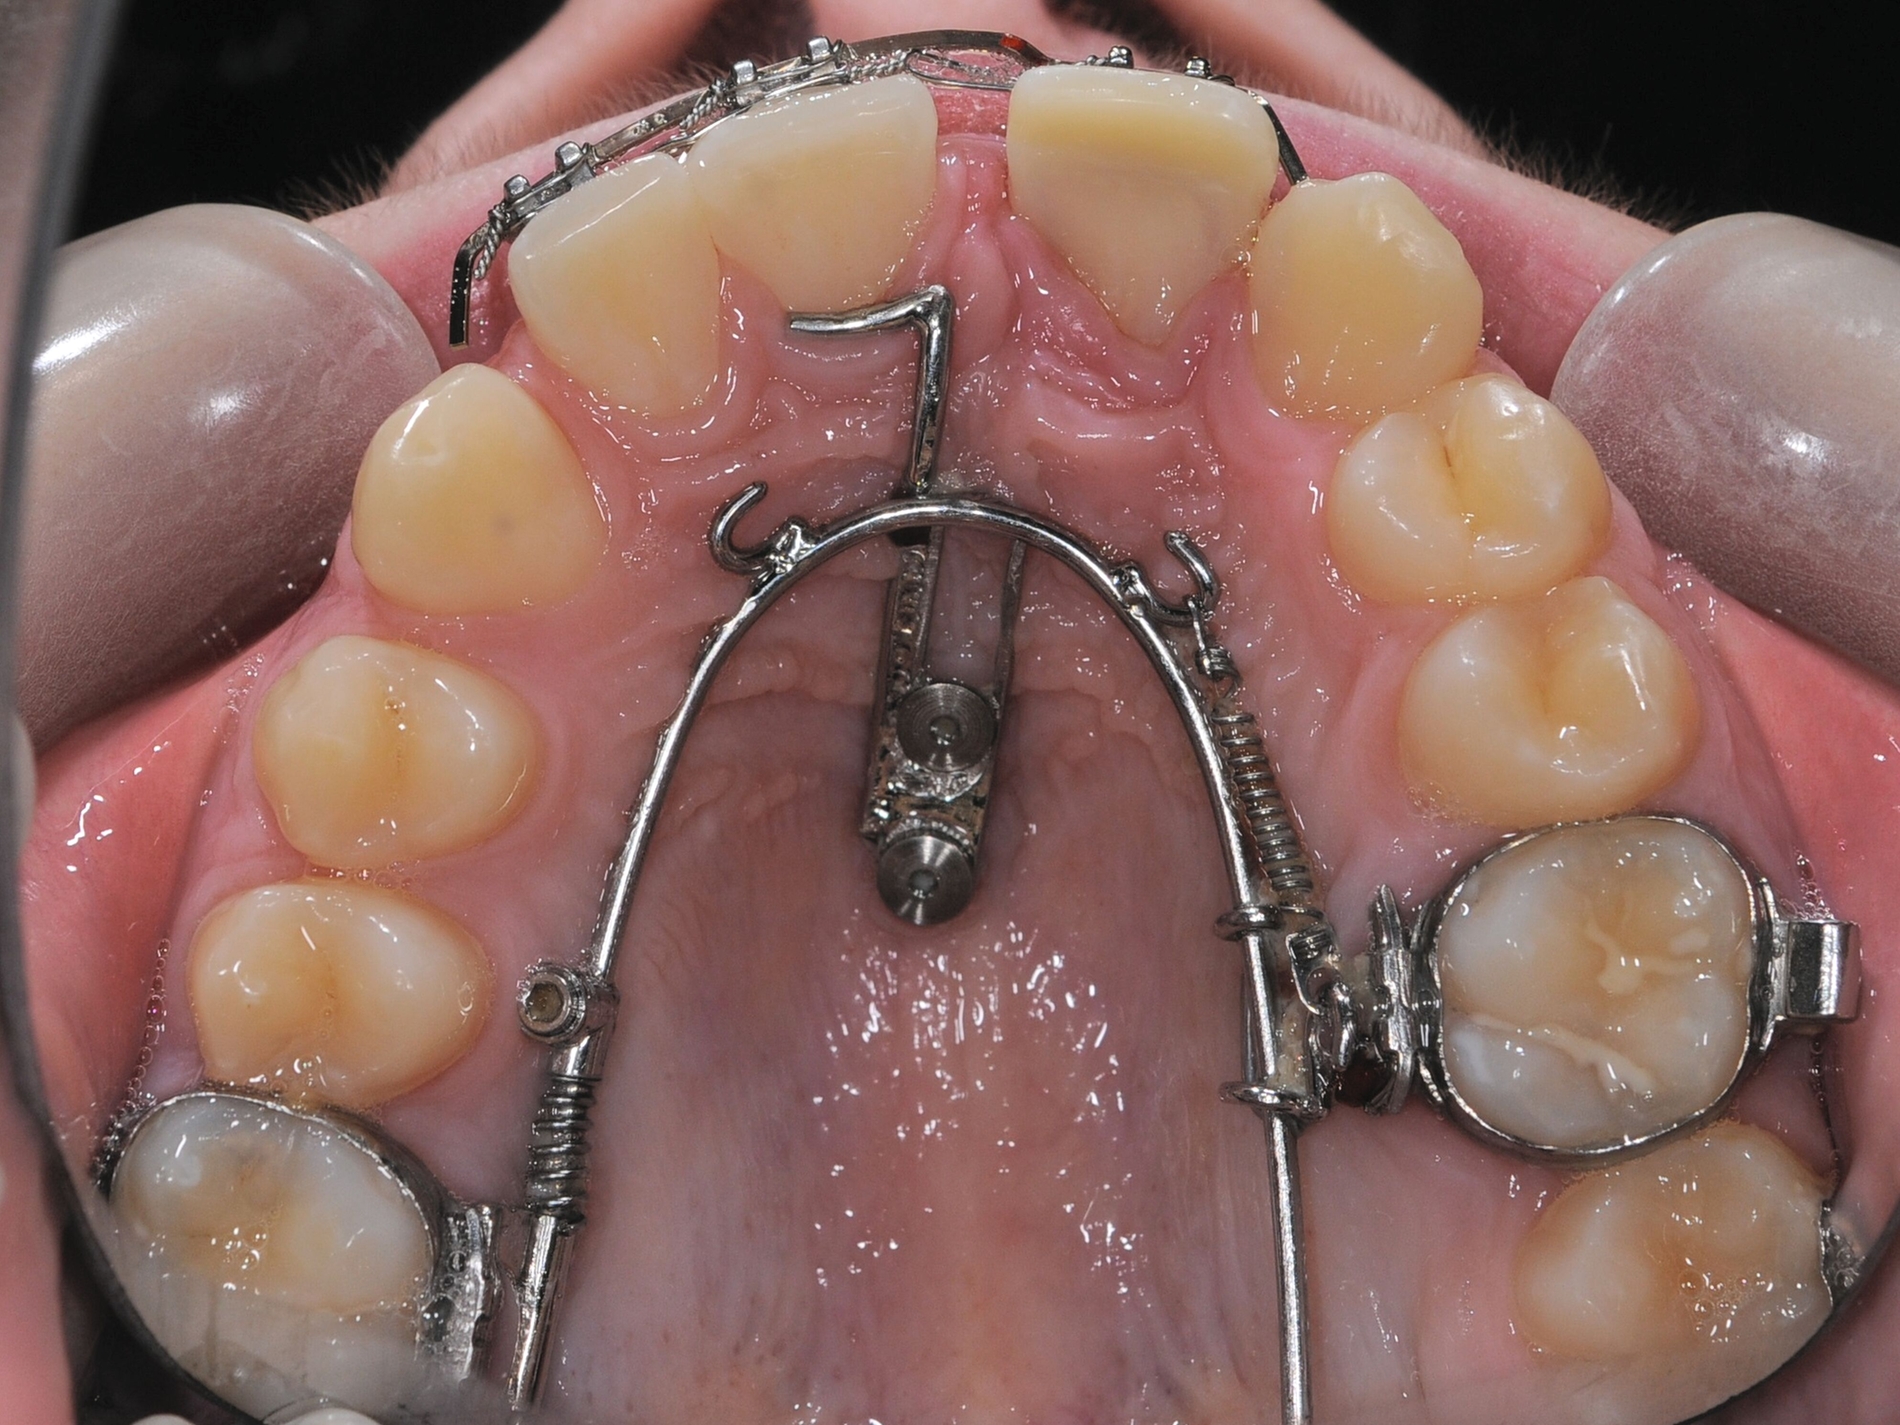

Eine Sonderform der kieferorthopädischen Extrusion ist die kieferorthopädische Extraktion, bei der die gesamte Wurzel langsam und kontrolliert aus der Alveole gehoben und am Ende extrahiert wird. Dieses Verfahren wird insbesondere dann angewendet, wenn ein Implantatbett mit ausreichendem Knochenangebot geschaffen werden soll [Bauer et al., 2019]. Schnelle und langsame Extrusionstechniken können jedoch auch bei einem Patienten kombiniert werden, wenn sowohl Anpassungen des Gingivaverlaufs als auch Veränderungen der Stumpfhöhe zur nachfolgenden Restauration geplant sind (Abbildung 2).

Schnelle kieferorthopädische Extrusionen im Sinne einer präprothetischen Maßnahme können zudem auch im Seitenzahnbereich indiziert sein, wenn für eine nachfolgende Kronenversorgung die notwendigen Voraussetzungen geschaffen werden sollen (ausreichende Stumpfhöhe, Einhaltung der biologischen Breite, Schaffung des Ferrule-Designs) [Gariulo et al., 1961; Juloski et al., 2012; Nugala et al., 2012] unter Einhalten eines Kronen-Wurzel-Verhältnisses von 1:1 [Grossmann und Sadan, 2005] (Abbildung 3).